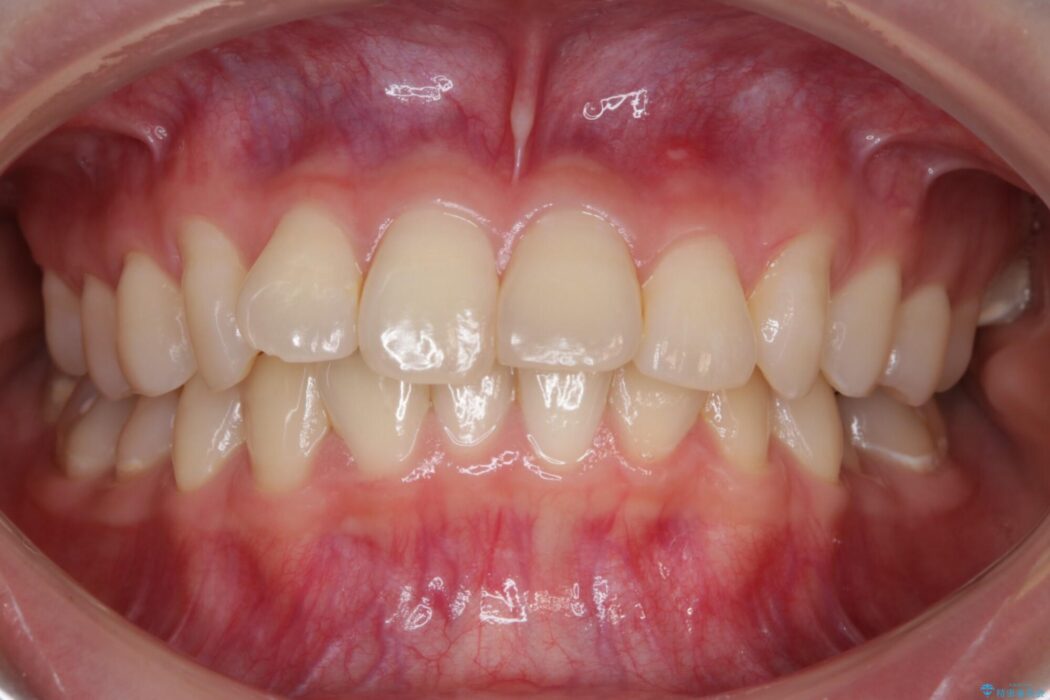

下の前歯のガタつきが気になるとご来院された患者様です。

インビザラインのライトパッケージにて、歯列拡大とディスキング(IPR)をを行いスペースをつくり非抜歯で治療を行いました。